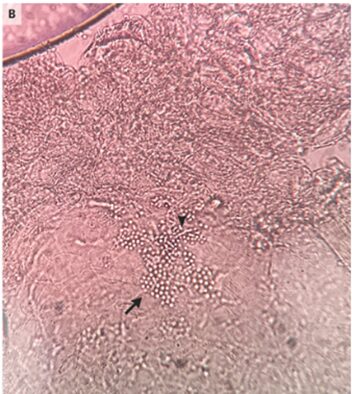

膿疱のKOHでは真菌の胞子と菌糸が示された。

以上から「新生児頭部膿疱症」と診断された